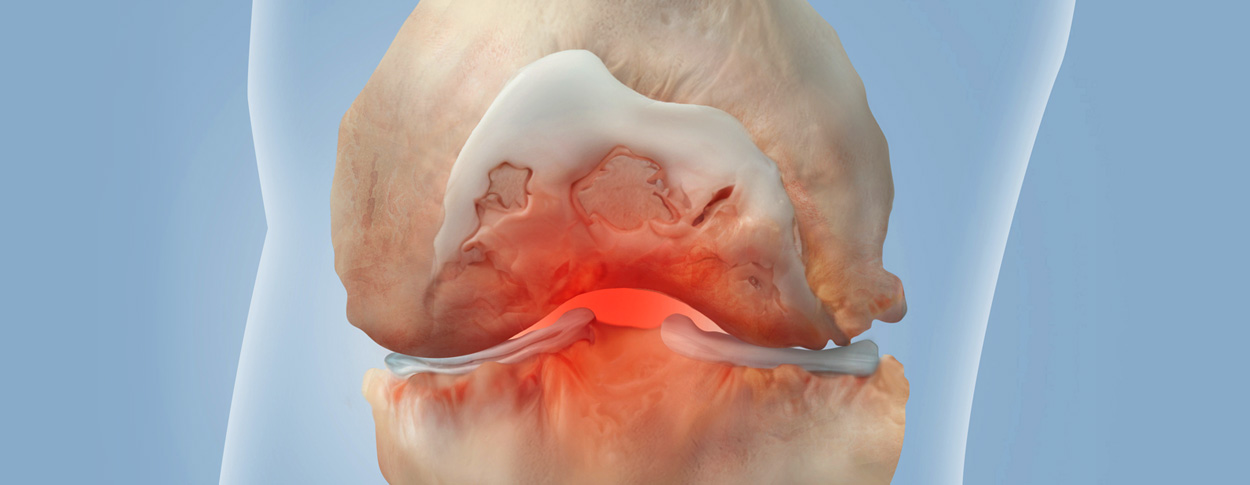

손상된 관절 연골을 재생시켜 관절 기능을 회복하고 통증을 완화하는 치료법입니다.

다양한 연골재생술 기법이 있으며, 환자의 상태와 손상 정도에 따라 적절한 방법을 선택합니다.

손상된 연골 부위에 작은 구멍을 뚫어 골수에서 나오는 줄기세포를 이용하여 연골 재생을 유도하는 방법으로 근본적으로 섬유연골(정상연골보다는 약한 연골)로 재생된다고 알려져 있습니다.